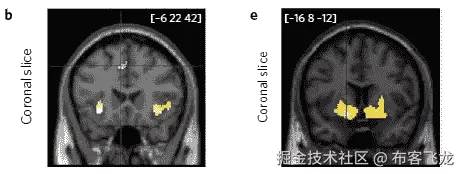

尽管这项行为实验的发现很有用,但作者的研究还有一个更有趣的转折。参与者在这些抽象符号之间做出的所有 24 个决定都是在他们躺在核磁共振成像仪里的时候做出的!通过这种方式,研究人员可以看到在做出每个选择和接收反馈时,大脑的哪些确切部分是活跃的。通过将行为数据与 fMRI 时间编码扫描配对,有可能区分出那些乐观的参与者和那些学习速度无偏见的参与者中显示活动增加的精确大脑位置。他们发现,对于乐观的学习者来说,在给予反馈时,纹状体和腹内侧前额叶皮层(vmPFC)的活动明显更多(在神经科学中,这被称为“奖励预测误差编码”)。

Areas of the brain that are activated during choice (left) and outcome (right) for optimistic reinforcement learning, α+.